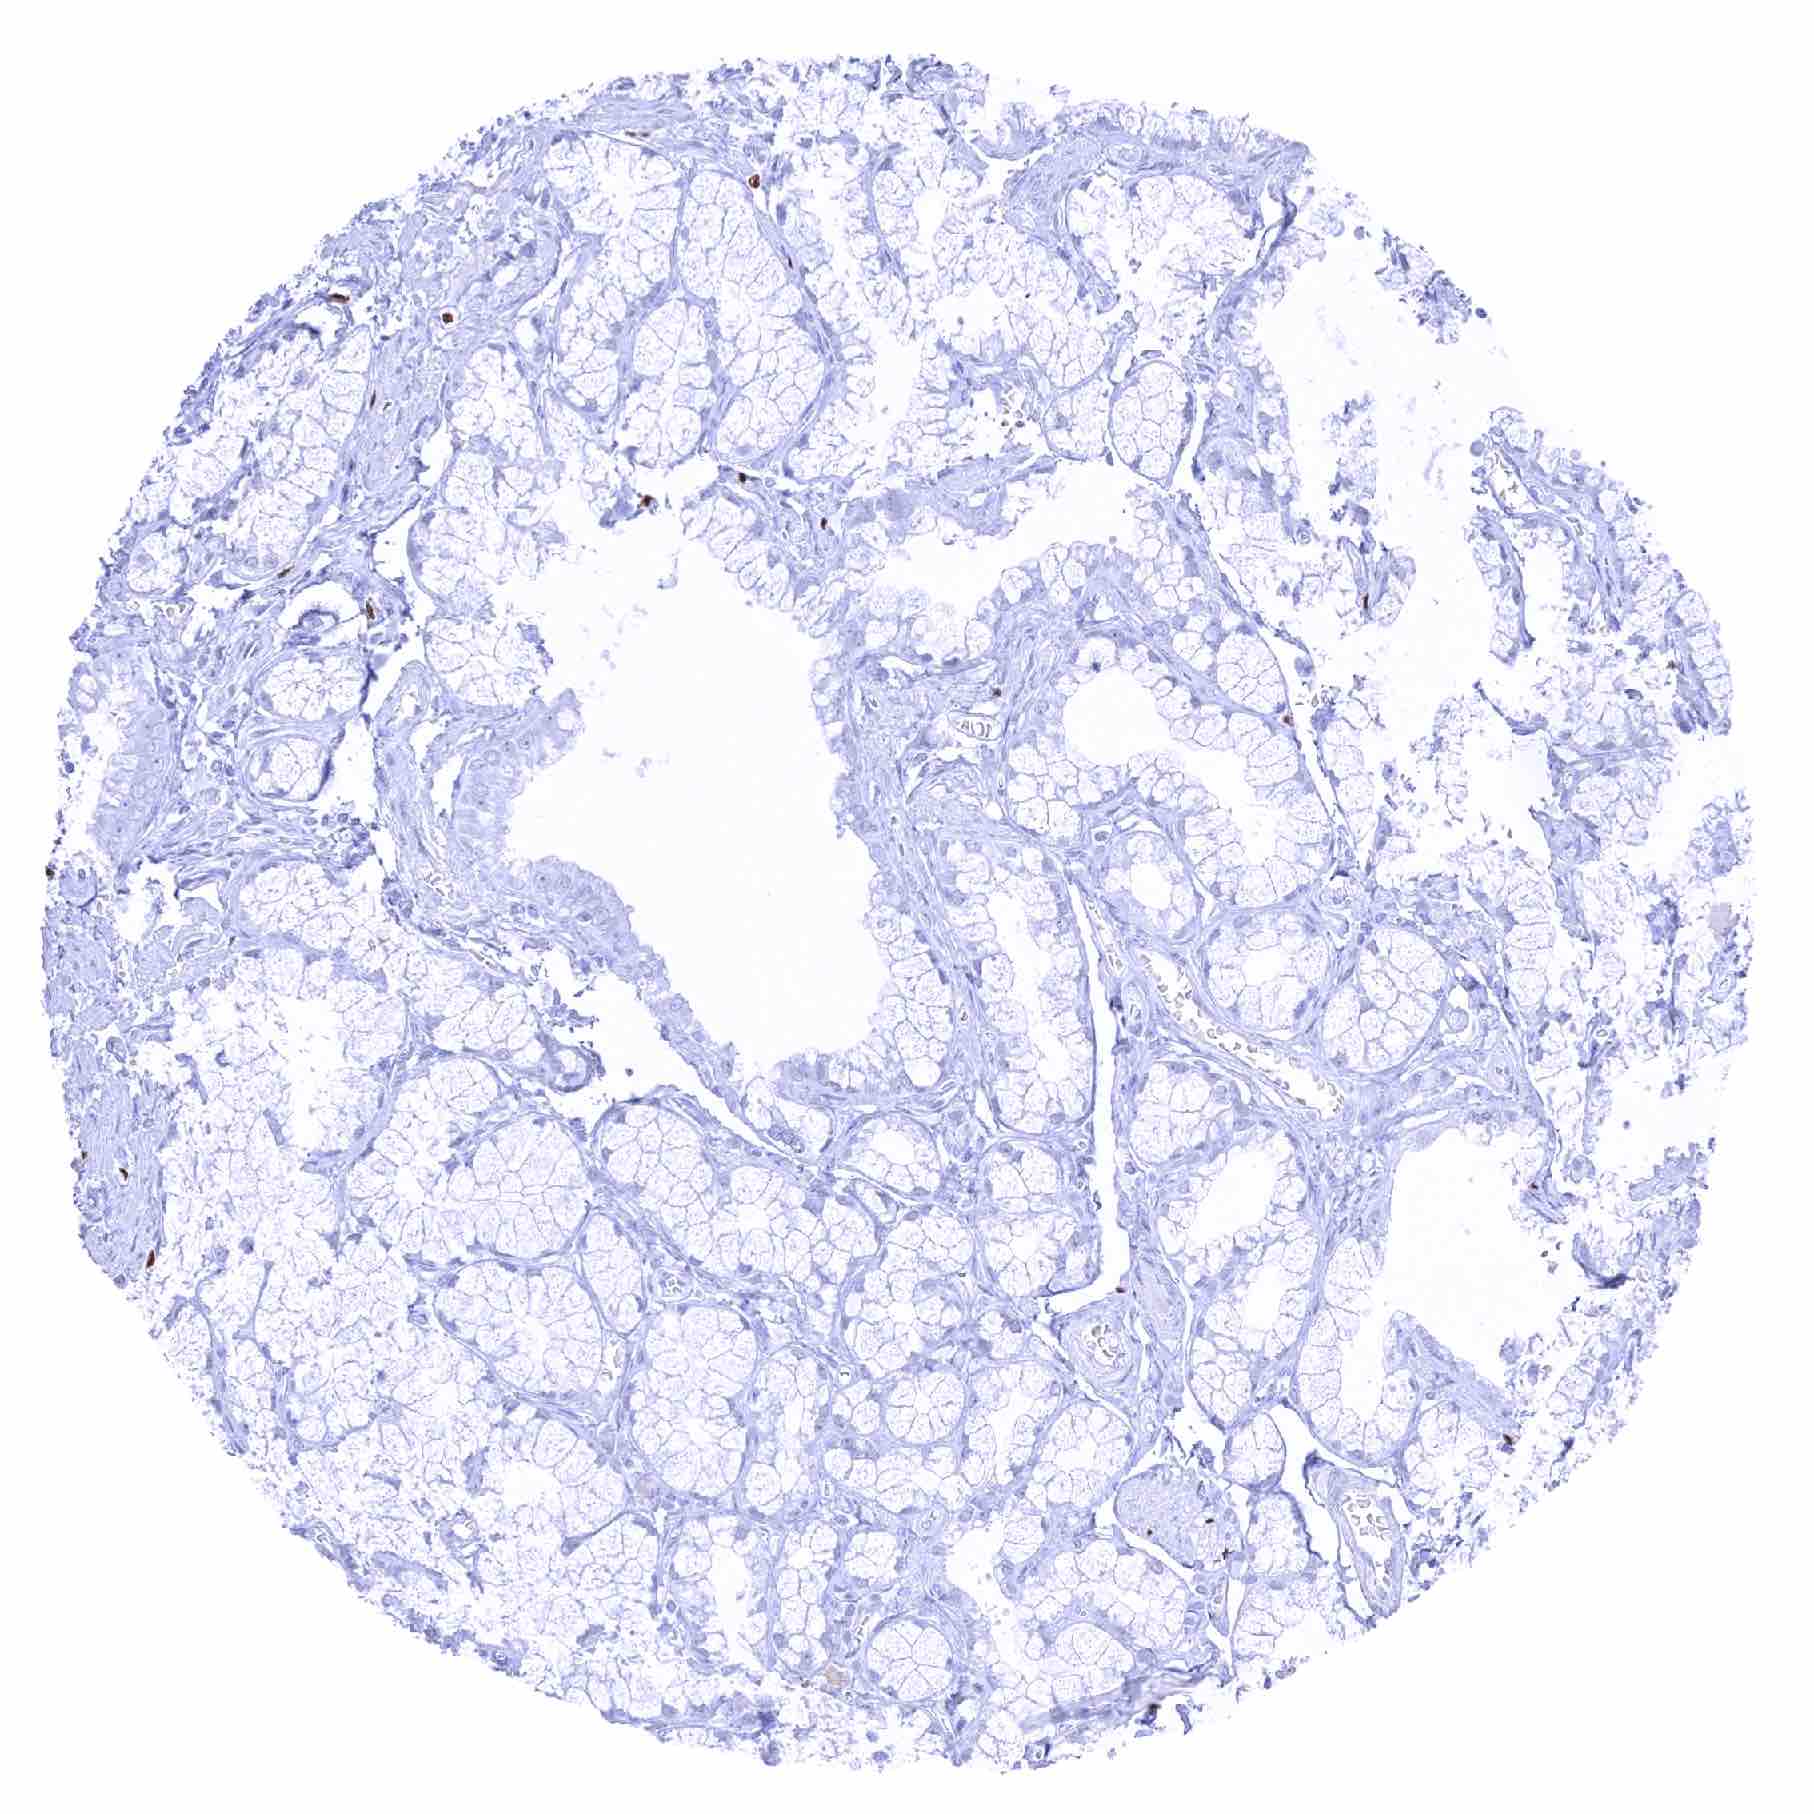

Pancreas